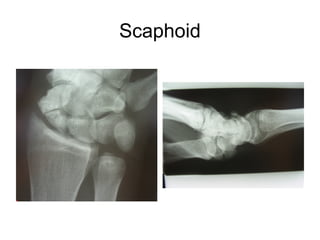

This document discusses several cases of scaphoid fractures in different patients. A 42-year-old female presented with carpal tunnel syndrome and wrist pain after a fall and was found to have a large cyst and fracture in her scaphoid bone. A 16-year-old male reported four months of painful wrist after a skateboarding injury. Imaging also showed a non-union in the wrists of a 42-year-old man bilaterally. Surgical treatment including open reduction and internal fixation with bone grafting was performed in some cases.